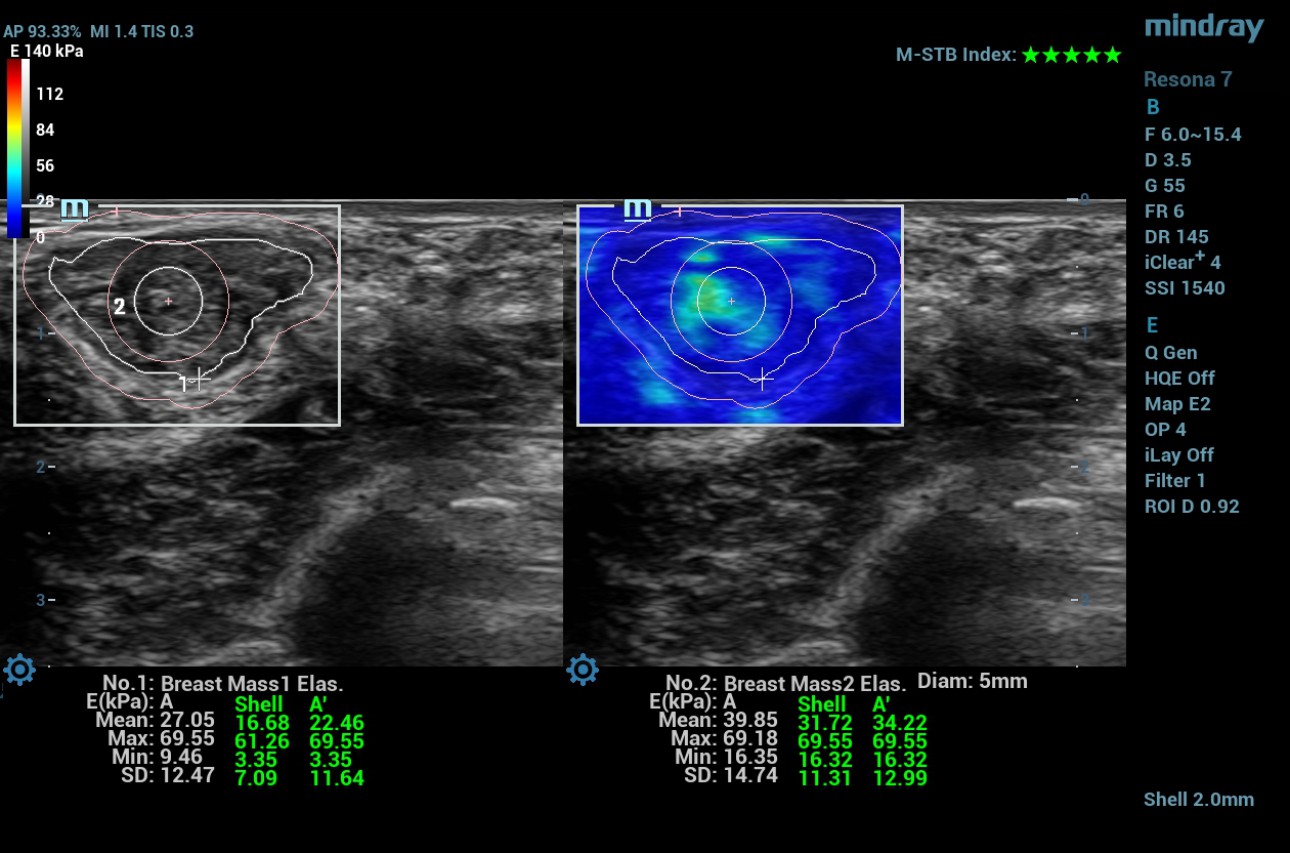

swe-prior-breast-mass-fig3-pc

Figure 3- SWE measurements of patient B

The Maximum and mean values in the selected ROI manually along the edge of the lesion are 69.5 kPa and 27 kPa. The maximum value in the 2mm shell around the lesion is 61.2 kPa. The maximum and mean values in the lesion + shell are 69.5kPa and 22.4kPa. Maximum and minimum values in the center of the lesion in a circular ROI measuring 5mm in diameter are 69.18kPa and 39.8kPa.